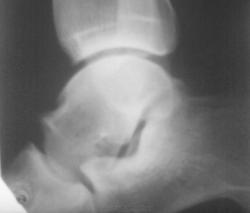

патологии не увидел.

А таранно-ладьевидный артроз и экзостоз по тыльному краю таранной кости.

Сустав этот выглядит необычно. Нет ли подвывиха? Нужна прямая проекция.

2. С ТАКОЙ таранной костью и ТАКИМИ остеофитами...и норма?))))...сомневаюсь я однако)))))

А что тут особенного? Суставные щели достаточные, равномерные, суставные поверхности не склерозированы. 1 - задний отросток таранной кости, 2 - по-моему скиалогическая штучка из-за нестрогобоковой проекции. Разве что 3 - структура?

Если не подвывих, то аномалия.

Мне не понравилась: 1) Разница ширины рентгеновских суставных щелей (стрелки).

2) С чем это пяточная кость сочленяется? Где кубовидная? Не слилась ли она с ладьёй?